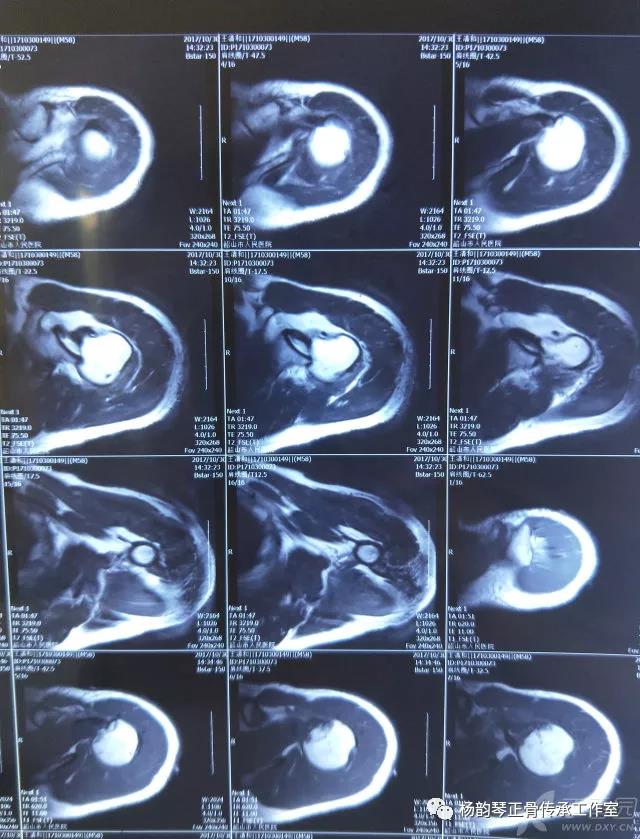

简要病史:骑摩托车跌倒致左肩部肿痛,活动受限,就诊于当地医院,拍片及磁共振检查后诊断为肩袖损伤及肩关节半脱位,予以悬吊固定,因症状缓解不明显就诊于我院。外院拍片情况如下:

应该说是一个典型的“灯泡征”影像,但是并未引起注意。

磁共振检查也完善了,还是报了个肩关节半脱位……影像科已经把坑挖好了……